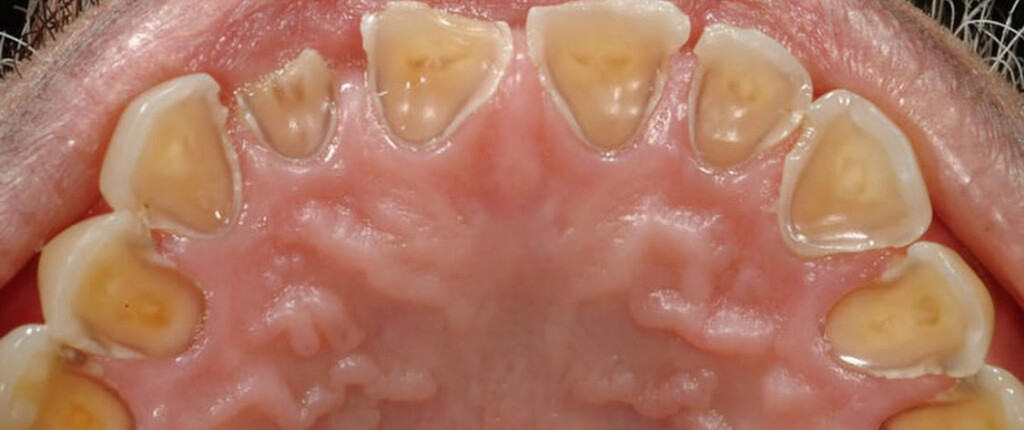

Symptoms: Common symptoms of teeth erosion include tooth sensitivity, tooth discoloration (yellowing), rounded or transparent edges of the teeth, and cracks or chips on the tooth surface.

Effects on Enamel: The enamel is the hardest substance in the human body, but it can still be eroded over time. When the enamel wears away, it exposes the underlying layer of the tooth called dentin, which is more sensitive and prone to decay.